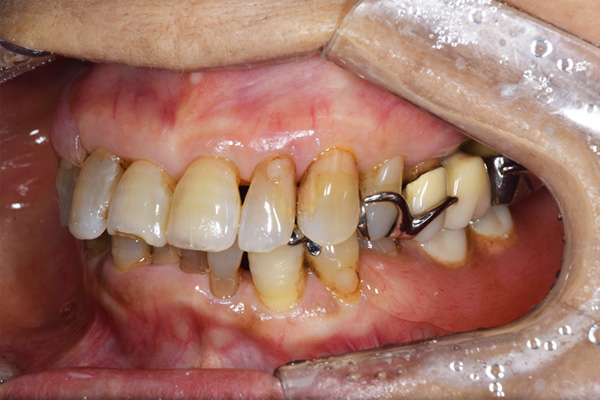

上下の入れ歯が外れやすくなったということでいらっしゃいました。 顎の骨はしっかりしていましたので、精密な型取りさえすればしっかりした入れ歯がつくれると思いました。 また下には6本歯が残っていましたが、虫歯になっている歯もありました。 かぶせ物のなかで大きな虫歯があった歯があり、1本だけ残せない状態でした。

上の入れ歯は確かに吸着は甘くなっていました。 また下の入れ歯はバネの一部が壊れており、安定感がなくなっていました。

ケース3(インプラントを用いた部分入れ歯)

右上と左下の歯がない方です。 上の入れ歯の安定が悪く、作り直したいとのことでいらっしゃいました。 今お使いの上の入れ歯を見てみると、口蓋部分が抜けており、安定性に欠ける構造になっていました。この入れ歯はノンメタルクラスプデンチャーといって、金属のバネを使用しない 入れ歯になります。これは見た目は良いのですが、歯への負担が大きいことと、入れ歯自体がやわらかいため、噛むには不便なことがあります。

右上のインプラント周囲炎で、その部分が痛いという患者様でした。 また奥歯で噛むことが難しかったため、前歯を使用することが多くなり、 前歯が前よりも前に出てきていることも気になっていらっしゃいました。

インプラント部以外にも歯周病が進行していましたので、歯周病の治療を行いました。 残念ながらインプラントと、1本の歯が残せなかったため抜歯を行いました。 その後、前歯の出っ張りを修正することと入れ歯の安定を図るため、残っている歯を全てかぶせ物にしていくことになりました。 写真中央は抜歯後に入れた治療用の入れ歯になります。 抜歯後歯ぐきが安定しましたら、入れ歯とかぶせ物の型取りを行いました。